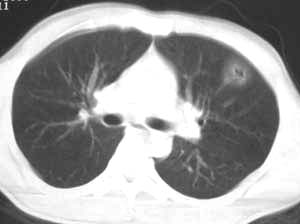

该病灶在纵隔窗没有显示,说明是渗出性病变,而且肺窗看起来也显得它非常淡薄。能造成锁骨骨折,说明受伤时所受冲击力不小。在大冲击力的情况下,胸部发生碰撞的机会非常大,很多患者在受伤后都说不清自己究竟是怎么着地以及究竟是何种姿势受伤。

一句话,有明确的外伤史,就要诊断肺挫伤.短期随访起到鉴别诊断作用.

有明确的外伤史,病灶呈渗出性改变,密度较低,边缘呈晕圈状改变,周围未见明显的异常血管影及纤维索条影和卫星灶。所以考虑是创伤性湿胸。

左肺上叶前段磨玻璃样结节,中心可见小结节样高密度影及空泡影,我个人觉得首先考虑恶性结节,结合病史,不能完全排除肺挫伤!建议薄层扫描后多方位重建,观察与支气管关系;定期复查,追踪观察(此类病变可能很长时间内不会发生改变),如果结节样高密度成分增多,建议手术切除.